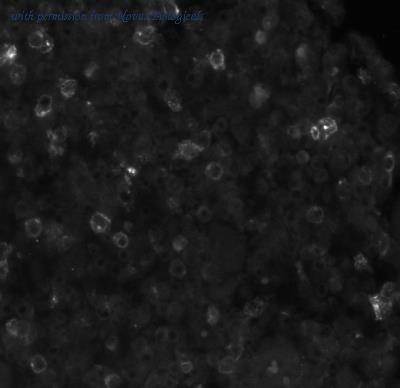

gene information - human OX40

- description:TNF receptor superfamily member 4